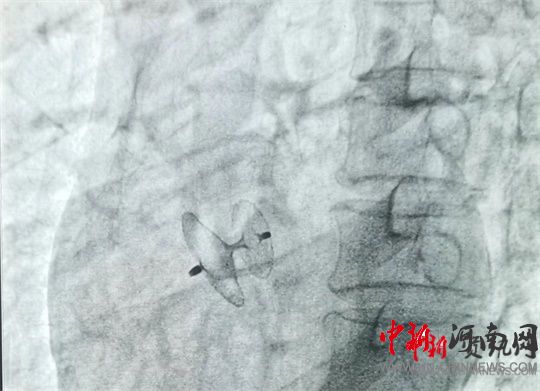

岳軍帶領(lǐng)團(tuán)隊(duì)將封堵器通過(guò)股靜脈送至卵圓孔處,展開封堵傘,使其與卵圓孔完美契合,成功封堵住缺口。經(jīng)床旁彩超證實(shí),無(wú)殘余分流,手術(shù)過(guò)程十分順利,全程僅用時(shí)60分鐘。術(shù)中及術(shù)后,患者均未出現(xiàn)不良反應(yīng),術(shù)后12小時(shí)即可下床活動(dòng)。